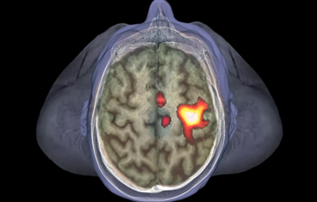

The main goal of the lab is understanding how the human brain builds a representation of the body in space, important for action and perception. To this aim, we use different techniques from cognitive neuroscience, including psychophysics, fMRI, intracranial EEG recording, neuropsychology and neural network modeling to study the multisensory mechanisms of underlying the representation of Peripersonal Space (PPS).